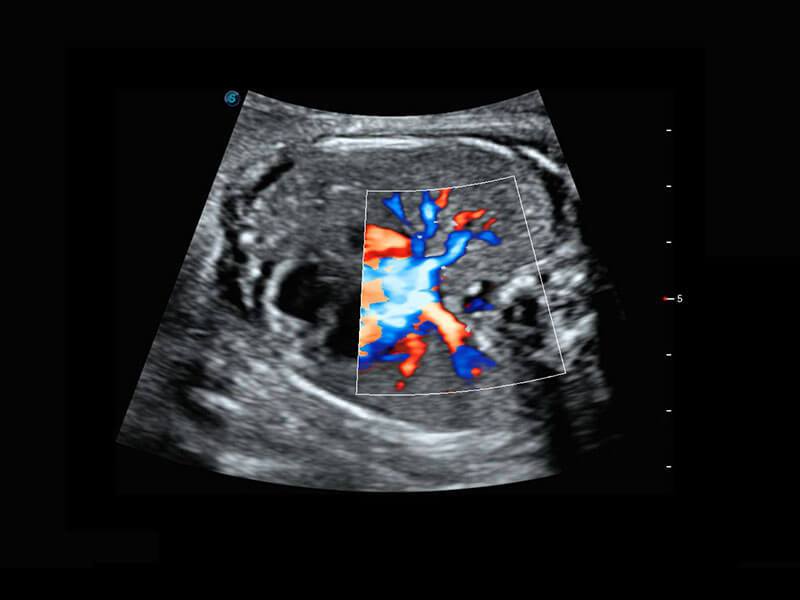

四腔心血流